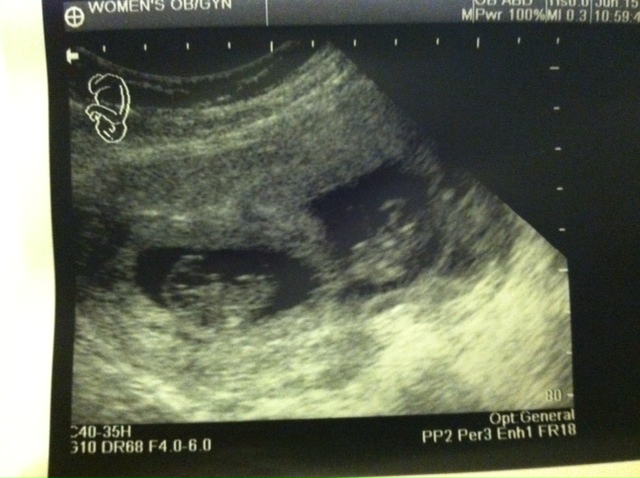

June 15, 2012 - 9 weeks, 5 days.